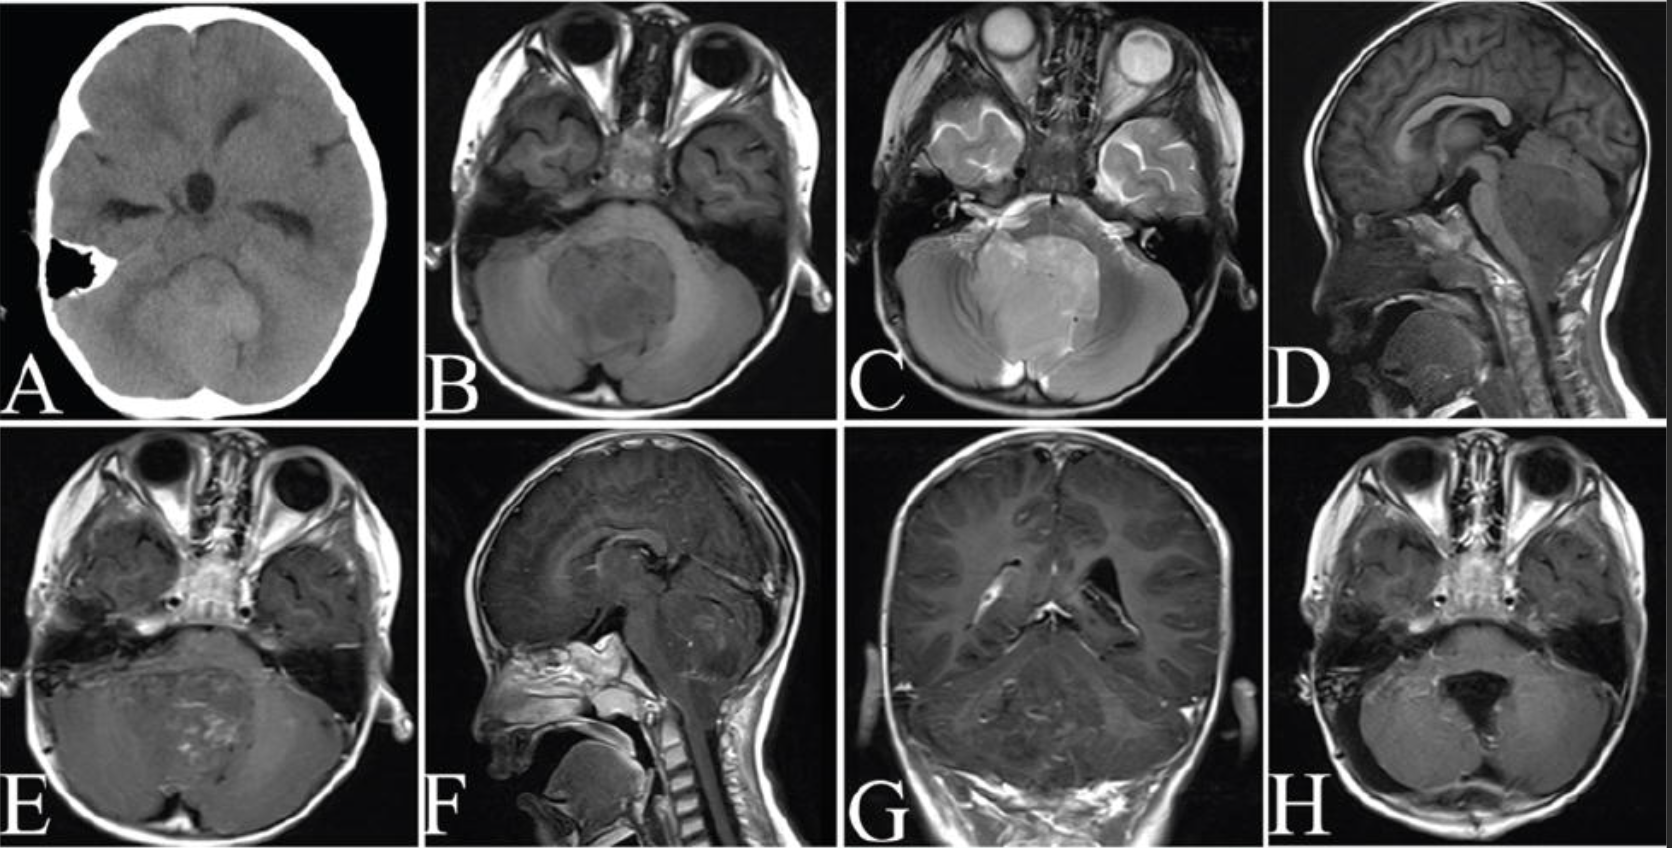

神经影像学表现

室管膜瘤,在MRI上表现为T1低信号,T2或质子密度像高信号钆增强通常很明显。

肿瘤常侵入第四脑室的外侧孔,从而引起脑积水,但肿瘤周围水肿罕见。在弥散加权成像序列中,室管膜瘤常呈现弥散受限表现。

室管膜瘤在CT上常为高密度均匀强化病灶,囊腔和钙化常见。第四脑室肿瘤内出现钙化强烈提示室管膜瘤,但不具诊断意义。

室管膜瘤大多起源于第四脑室,在弥散加权像上常为弥散受限表现。此特征有助于区分颅后窝的与毛细胞型星形细胞瘤。